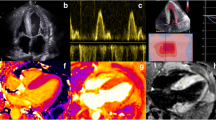

The response to chemotherapy has traditionally been classified by assessing the reduction in FLC, and this classification has subsequently been used to assess whether a haematological response correlates with stabilisation or even regression of CA. An early study of 41 patients, which defined haematological response as a reduction in FLC > 50%, demonstrated that haematological response had a weak correlation with reduced E/e’ and left atrial stiffness, but did not result in GLS improving [76]. In contrast, a retrospective analysis of 61 patients, which separated patients into complete responders (normal FLC ratio and negative serum/urine immunofixation) and non-complete responders, demonstrated that complete responders had a significant improvement in LS, and this correlated with reduced brain natriuretic peptide (BNP) and troponin-I. Interestingly there were no changes observed in wall thickness, ejection fraction (EF) or diastolic function [77]. These findings are supported by a recent study of 915 patients, which concluded those achieving a complete haematological response had improved LS, compared to those who did not, and was associated with reduced N-terminal pro-BNP and all-cause mortality (Fig. 1) [78••]. Based on these findings, it appears a complete haematological response, rather than a partial response is required to improve LS. Even a small residual amount of AL amyloid is likely to exert pathological cardiotoxicity and prevent cardiac recovery. Improved LS acts as a surrogate marker for a good treatment response, and reduced mortality.

Top panel: echocardiographic global strain (GS) measurements demonstrating an improvement in a patient with a good haematological response to chemotherapy, and a deterioration in another patient with a poor haematological response. Bottom panel: cardiac magnetic resonance imaging demonstrating a reduction in native T1, late gadolinium enhancement (LGE) and extracellular volume (ECV) in a patient with a good haematological response to chemotherapy, and a deterioration in another patient with a poor haematological response

A recent retrospective analysis sought to evaluate the use of serial CMR scans in monitoring treatment response in 31 patients with AL-CA. A complete haematological response was achieved in 36%, and a very good response (defined as FLC < 40 mg/dl) in 29%. A significant reduction in ECV attaining the CMR criteria for CA regression occurred in 13 patients, and a complete or very good response was associated with a reduction in ECV (92%). The reduction in ECV led to a reduced LV mass in 7 (54%) patients who regressed, and was associated with an improved LGE pattern in 5 (38%) patients. This demonstrates that cardiac regression occurs in a significant number of patients who respond to treatment. The reversal of LGE seen in those with a reduction in ECV is compelling evidence that this reduction is not just due to a reduction in myocardial oedema, but also CA regression (Fig. 1) [83•].